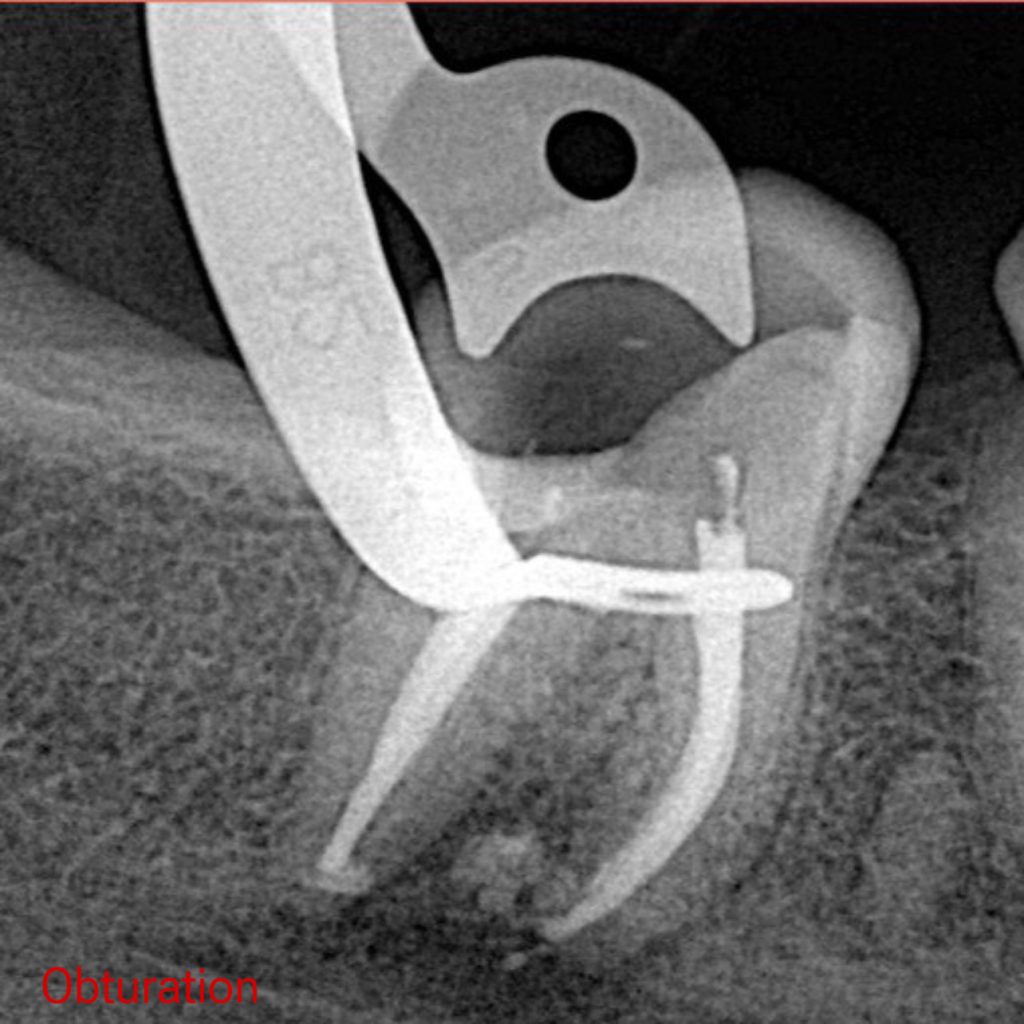

X ray showed many problems in previous Endodontic treatment with overhang amalgam filling

– Endodontic Re-treatment done, Obturation with Bioceramic Sealer and single cone

The pain completely resolved after obturation visit